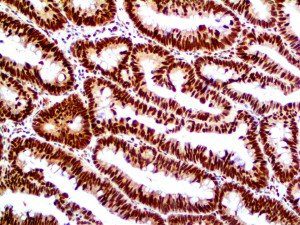

The first cytokines released are interleukin 1β (IL-1β) and tumor necrosis factor-α (TNF-α), which attract a variety of circulating white blood cells (WBCs) to the infection site, including neutrophils, monocytes, macrophages, and natural killer (NK) cells. This response, along with the antipathogenic chemicals released by these cells (i.e., complement), comprise the innate immune response. These cells directly attack the invading pathogen and also release additional cytokines, chief among them interleukin-1 and 6 (IL-6). IL-6 is essential for invoking the adaptive immune response, which calls T-cells, B-cells, and T helper (Th) cells to the infection site. IL-6 also stimulates further recruitment, proliferation and activation of macrophages.

This activation induces inflammatory monocytes to highly express IL-6, starting a localized and then systemic cascade effect that results in hyperproduction of IL-6, which accelerates the inflammatory process. Because IL-6 also increases vascular permeability, excessive levels cause blood vessels to become very leaky. This, along with clotting factors released from vascular endothelial cells, stimulates the coagulation cascade, resulting in microthrombosis (tiny clots), which leads to ischemia and tissue death of the kidney, intestines, heart, liver, brain and extremities.